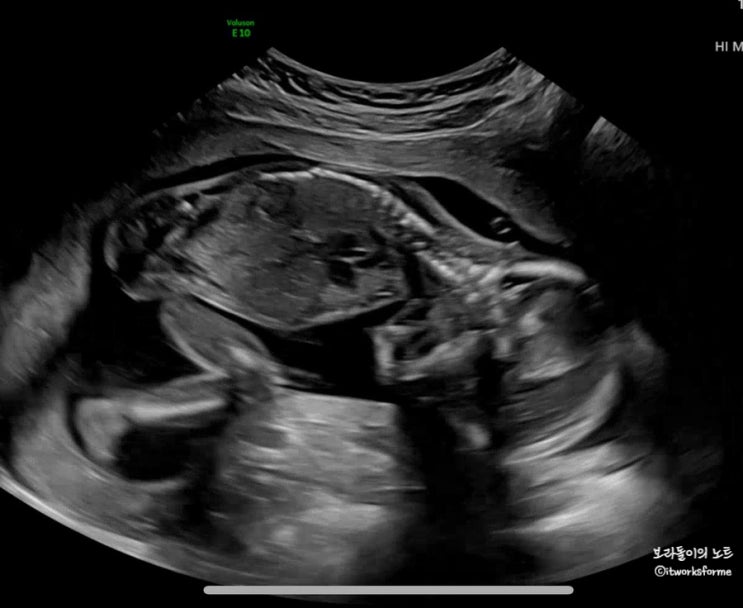

임신 20주 초음파 정기검진, 성별 확정!!

드디어 #임신20주 임신 5개월이 되었으니 임신기간의 절반까지 왔다! 태아검진휴가를 내고 #임신20주초음파...